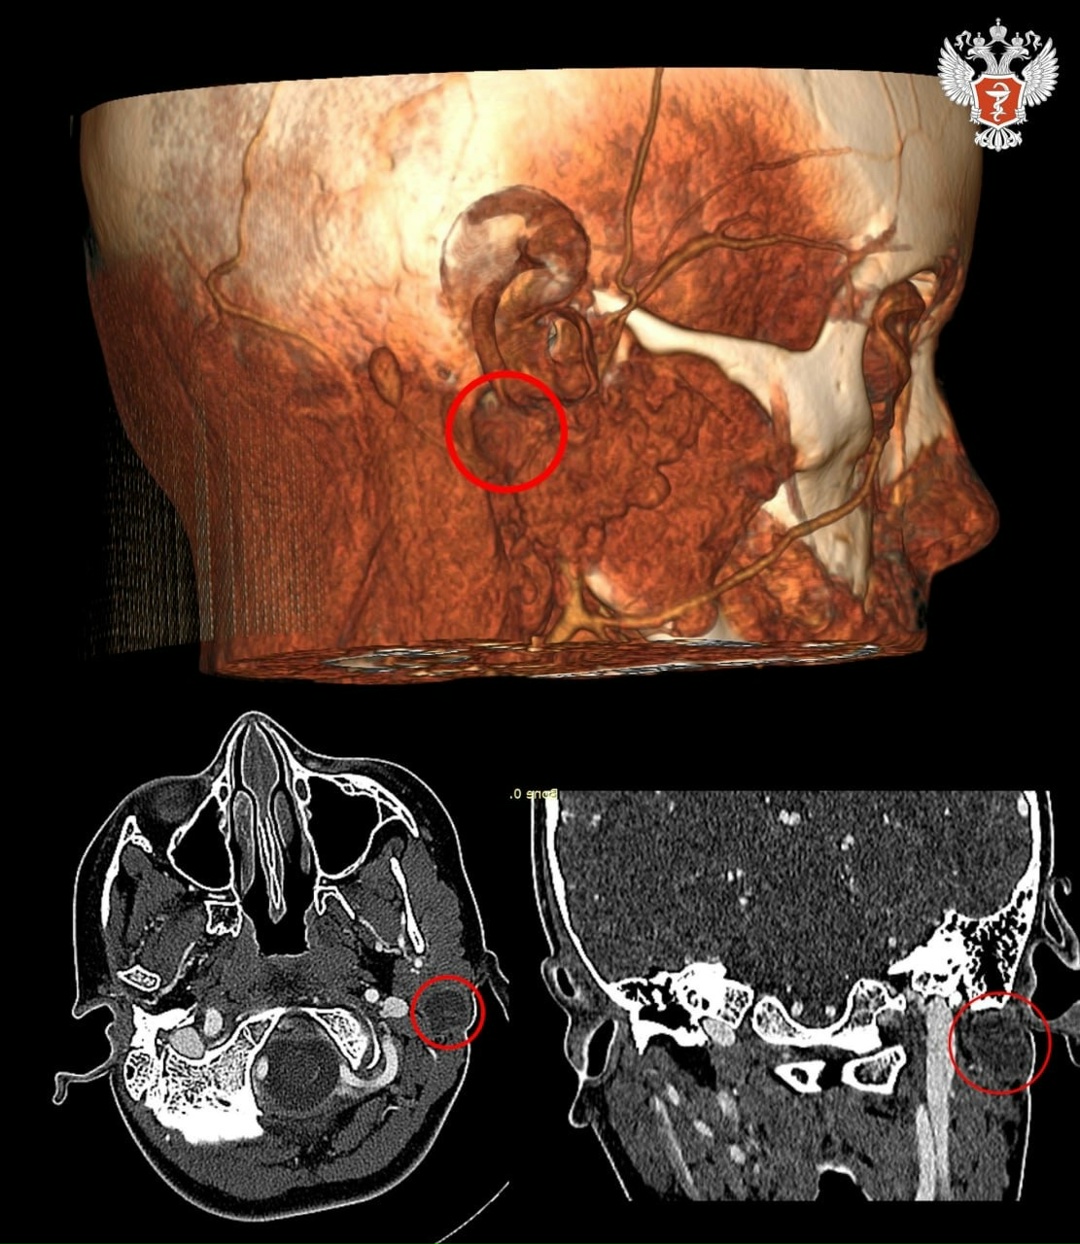

Семилетняя пациентка из Сыктывкара поступила в Российскую детскую клиническую больницу Минздрава России. Девочка три года страдала от образования, которое встречается реже, чем в одном случае на миллион, — кисты первой жаберной щели. Патология вызывала постоянные воспаления, нагноения и боли.

— Эта киста образуется в результате аномального развития тканей, из которых у эмбриона формируются все ткани в области головы и шеи. Выстланный изнутри эпителием тяж постоянно вырабатывает кожное сало, что создает идеальные условия для развития инфекционного процесса — любая грязь вызывала серьезные воспаления», — объяснил заведующий отделением челюстно-лицевой хирургии РДКБ Минздрава России Александр Кугушев.

➡️ Сложность лечения заболевания обусловлена не только его редкостью, но и анатомическим расположением кисты — в глубине тканей она прилегает к жизненно важным крупным сосудам и лицевому нерву, повреждение которого грозило асимметрией лица и потерей мимики.

В результате врачи удалили кисту через один небольшой разрез за ухом, избежав повреждения всех прилегающих структур. Разрез скрыт в естественной складке за ухом, и на лице ребенка не осталось ни одного видимого шрама.